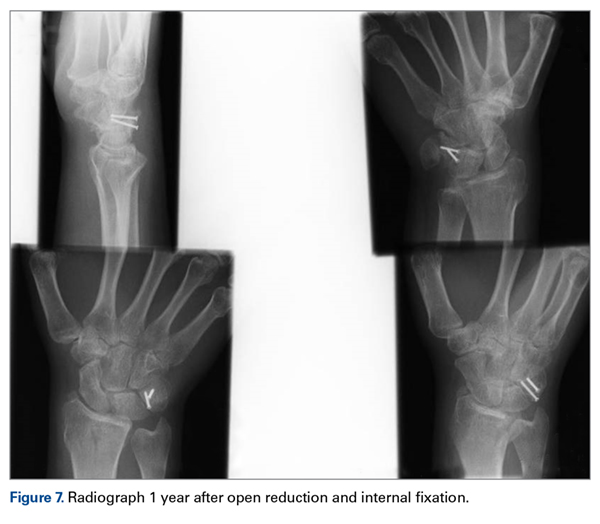

The other carpal fractures were nondisplaced and fixation was not required. The wrist was immobilized in a full cast. At 4 weeks, K-wire and cast were removed and the wrist mobilized under supervision of a hand therapist. Satisfactory radiologic union was noted at 6 weeks. Further follow-up was arranged at 3 months, 6 months, and 1 year ( Figure 7 ). At 6 months, the patient had full range of motion and good grip strength. At 12 months, the outcome was excellent (Mayo Wrist Score = 90).Discussion